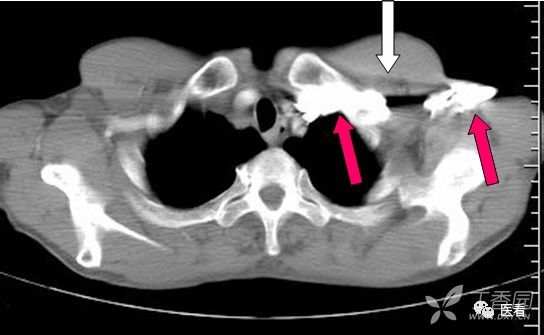

8 受检者自身结构与设备双重原因

亨氏暗区

颅底(致密)骨产生的横行或放射状伪影,与设备性能也有关系

下图为16拍MSCT,伪影较轻。

此图为双排螺旋 CT图像, 伪影较16层及以上MSCT显著的多。